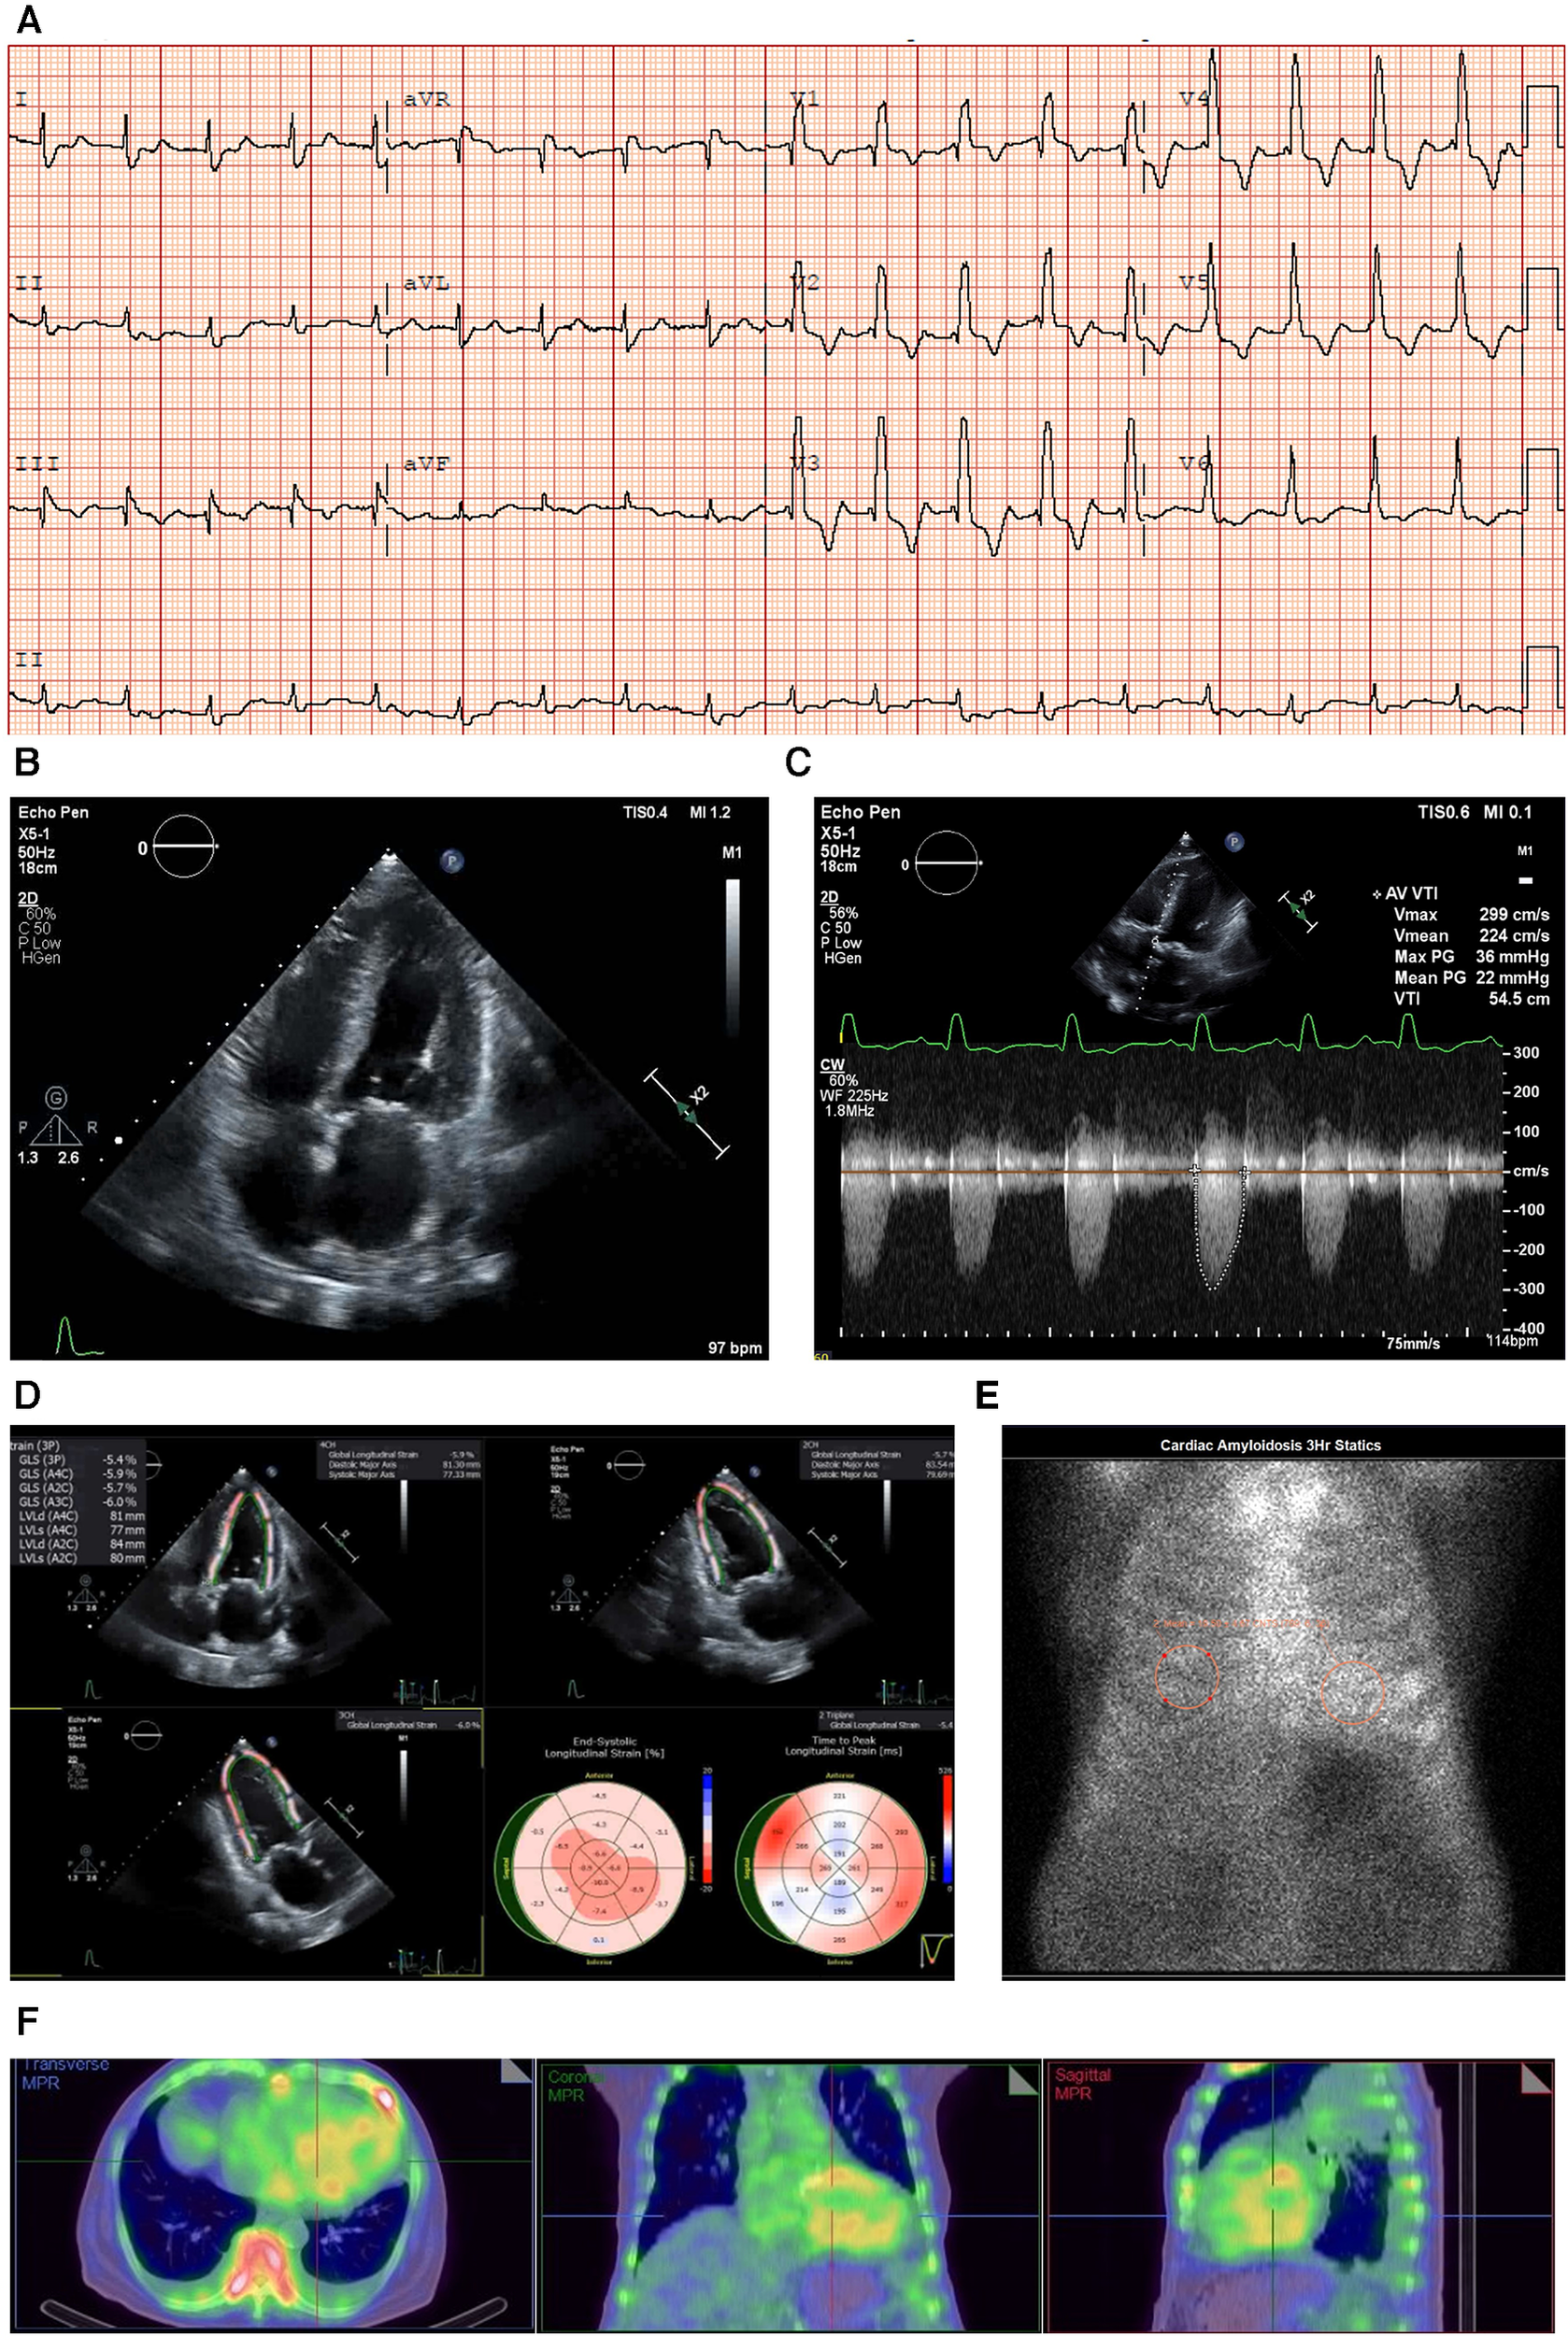

Figure 1

Case 1 clinical investigations. (A) An ECG showing sinus rhythm with first-degree heart block and RBBB morphology, and corrected QT interval prolonged for a heart rate of 98 bpm. (B) A 2D echocardiography with a four-chamber view showing LV hypertrophy with biatrial dilatation. (C) Continuous-wave Doppler of the AV consistent with low-flow/low-gradient AS. The calculated AV area was 0.47 cm2. (D) An echocardiography GLS showing markedly reduced GLS with apical sparing, typical of a diagnosis of CA. (E) A planar bone scintigraphy (99mTc-PYP) scan at 3 h with a H/CL ratio of 1.33. (F) SPECT-CT fusion showing an intense myocardial uptake with a clear LV cavity, excluding the presence of a blood pool.

AS, aortic stenosis; AV, aortic valve; CA, cardiac amyloidosis; ECG, electrocardiogram; GLS, global longitudinal strain; H/CL, heart to contralateral lung; LV, left ventricular; RBBB, right bundle branch block; SPECT-CT, single-photon emission computed tomography; 99mTc-PYP, technetium pyrophosphate.

An echocardiogram revealed concentric LV hypertrophy (interventricular septum of 1.3 cm; posterior wall measuring 1.4 cm; a relative wall thickness of 0.7, demonstrating significant hypertrophy) with an EF of 33 ± 5% and a moderate biatrial dilatation (R) (Figure 1B). Mild mitral stenosis was observed, and the mean mitral valve gradient was 4 mmHg. Severe AV stenosis was caused by a calcified valve, and the AV area was 0.47 cm2 (Figure 1C). The peak gradient was 40 mmHg and the mean gradient was 25 mmHg, demonstrating low-flow/low-gradient AS. The stroke volume index (SVi) was 17.2 ml/m2 and the E/A ratio was 3 (R). Red flags seen on the echocardiogram included atrial septal thickening and a markedly reduced global longitudinal strain of −5.41 with relative apical sparing (Figure 1D).

Due to the strong clinical suspicion for CA, a 99mTc-PYP scan was performed, which demonstrated a heart-to-contralateral lung (H/CL) ratio of 1.33 at 3 h (Figure 1E). Single-photon emission computed tomography (SPECT-CT) scans revealed an intense myocardial uptake (Figure 1F).